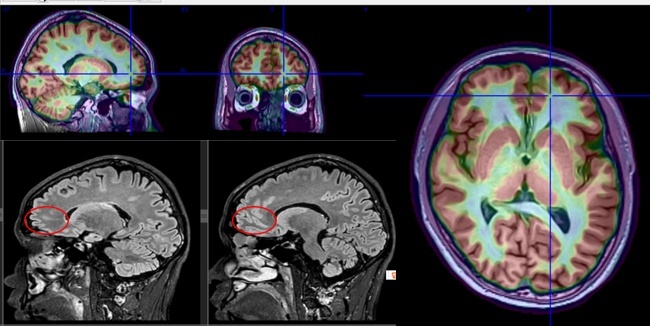

癫痫中心刘晓蓉教授、何娜教授、胡湘蜀主任医师领衔的内科和神经电生理团队联合神经外科胡滨主任医师、放射科副主任利晞教授、核医学科主任姜圣男教授等专家展开多学科会诊(MDT),综合症状学、神经影像、电生理、基因检测等结果全面深入的评估,确定其致病元凶为位于大脑 “左侧额极沟底”的局灶性皮质发育不良(FCD)。

(头MR及PET-MR显示左额额极沟底FCD)